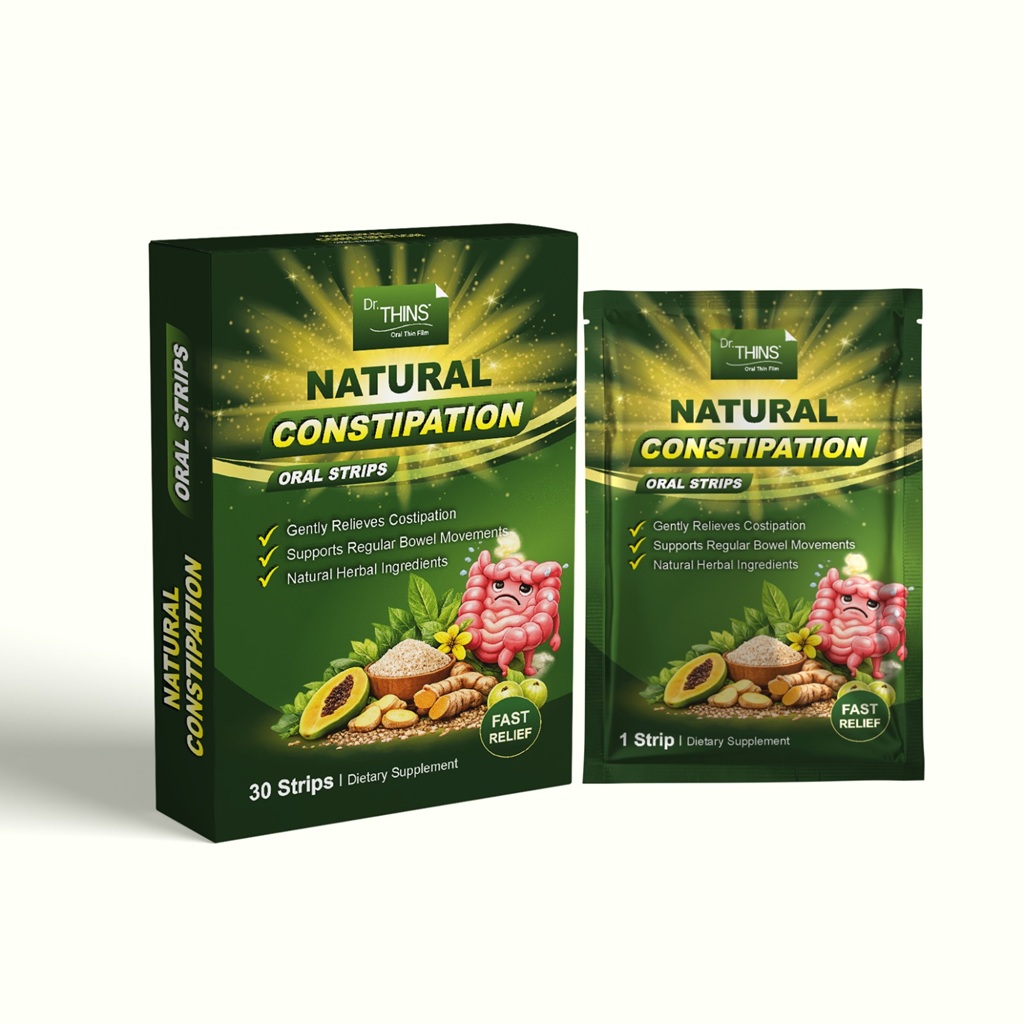

Gastrointestinal

Wellness Products

Wellness Products

Livkon Pharmaceuticals, one of the best ORO dispersible film manufacturers aims to help patients who have a tough time taking medicines. It is also a better option from the patient’s point of view as it prevents choking. Similarly, it also prevents the patient from rejecting the drug as no swallowing or chewing is involved. Many problems like bloating and inflammation and other problems can be easily solved with an orally disintegrating strip like Simethicone